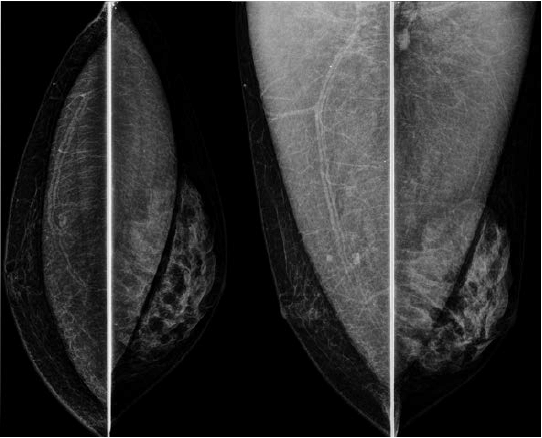

Assinale a alternativa que apresenta corretamente o que observa-se na análise das imagens da mamografia.

A

Reconstrução mamária com tecido adiposo pós-mastectomia, à direita.

B

Injeção de silicone líquido retropeitoral, à direita, em mama masculina.

C

Proliferação de tecido glandular, à esquerda, em mama masculina.

D

Implante mamário retropeitoral bilateral e nódulo na mama esquerda.

E

Mamoplastia redutora bilateral com esteatonecrose na mama direita.